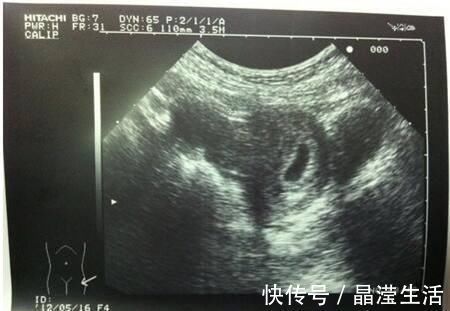

心管|怀孕两个月,检查没有胎心胎芽,检查只有个空壤这是什么情况啊?

你好很高兴能为你解答,希望能帮到你!如果平时月经周期规律,那么怀孕两个月还没有胚胎芽及心管搏动则多数提示胚胎停止发育,预后不好,不过临床上也不完全是这样,简要分析如下:

2、如果既往月经规律,那么要结合超声及激素水平的情况来判断是否是胚胎发育异常,一般HCG3-5万即可见到胚芽心管搏动,孕囊达到2cm超过一周还没有见到心管搏动,则停育可能性大。